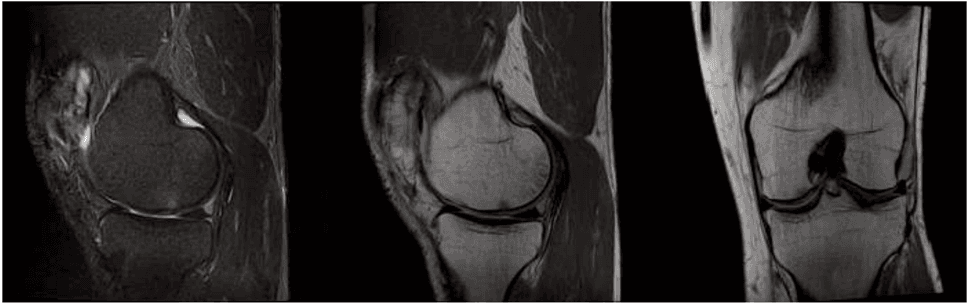

Chaque cas d'arthrose est unique et nécessite une analyse méticuleuse avant de procéder à toute intervention. Dans notre clinique à Milano, le parcours commence par une consultation spécialisée approfondie soutenue par des examens diagnostiques par imagerie, tels que l'IRM ou l'échographie haute résolution. Cette phase est cruciale pour déterminer le degré d'usure articulaire et l'aptitude du patient à la médecine régénérative.